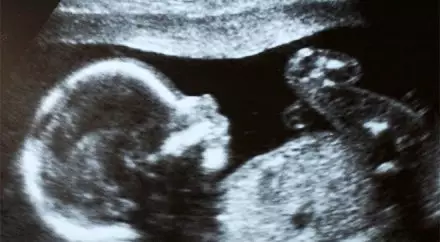

Чилийские врачи случайно обнаружили в утробе 92-летней женщины мумифицировавшийся плод возрастом 50 лет, сообщает РИА Новости. Пожилая пациентка обратилась в госпиталь Сан-Антонио с болями в животе после неудачного падения.

Врачи сделали рентген и выяснили, что внутри нее находится неродившийся плод с периодом вынашивания в 30 недель, он был зачат примерно 50 лет назад. Женщина не подозревала о своей беременности, а плод по неизвестным причинам погиб и мумифицировался, поэтому не создавал для чилийки особых проблем все эти годы. По итогам обследования врачами было принято решение оставить плод на месте, так как попытки извлечь его представляли бы опасность для престарелой женщины. Сейчас она чувствует себя лучше и переведена на домашнее лечение последствий полученной при падении травмы.